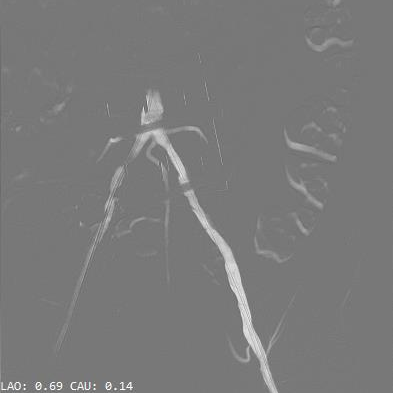

根部造影:可见瓣叶活动僵硬,无反流

18mm球囊预扩,无腰无漏,遂确定选用AV23瓣膜

AV23瓣膜初始定位,瓣上1mm

180bpm起搏下,配合导丝张力,瓣膜稳定释放至工作位

工作位造影,左右重合位下,无窦侧瓣下2mm,小弯侧半个菱形格,瓣膜形态好、同轴性佳

多角度评估,左冠切线位下,瓣膜形态呈类直角梯形,结合术前CT,无窦侧钙化为主,水平夹角不大,小弯侧深度可接受,脱钩趋势保持不变或小弯侧→大弯侧轻微,遂决定完全释放

瓣膜稳定脱钩释放

根部造影,瓣膜形态良好,位置理想,小弯轻微瓣周漏(预估左右融合嵴处);猪尾导管测压无压差